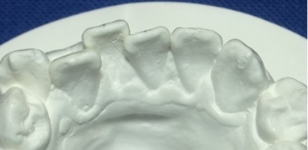

観察方法はPARスコアではなく、もう少しダイレクトな評価になるリトル教授らの方法を使いました。つまり右図のように、後戻りが一番現れやすいと言われている下の前歯において、歯と歯の接触点間の距離をmm単位でデジタル写真上で計測し、それらの合計のミリ数を「指数」とするものです。歯並びが綺麗であれば“0”に近い数字になり、数字が大きいと悪い歯並びを意味します。この写真の歯と歯の接触点間の距離の合計は9.3mmでしたから、指数は9.3になります。